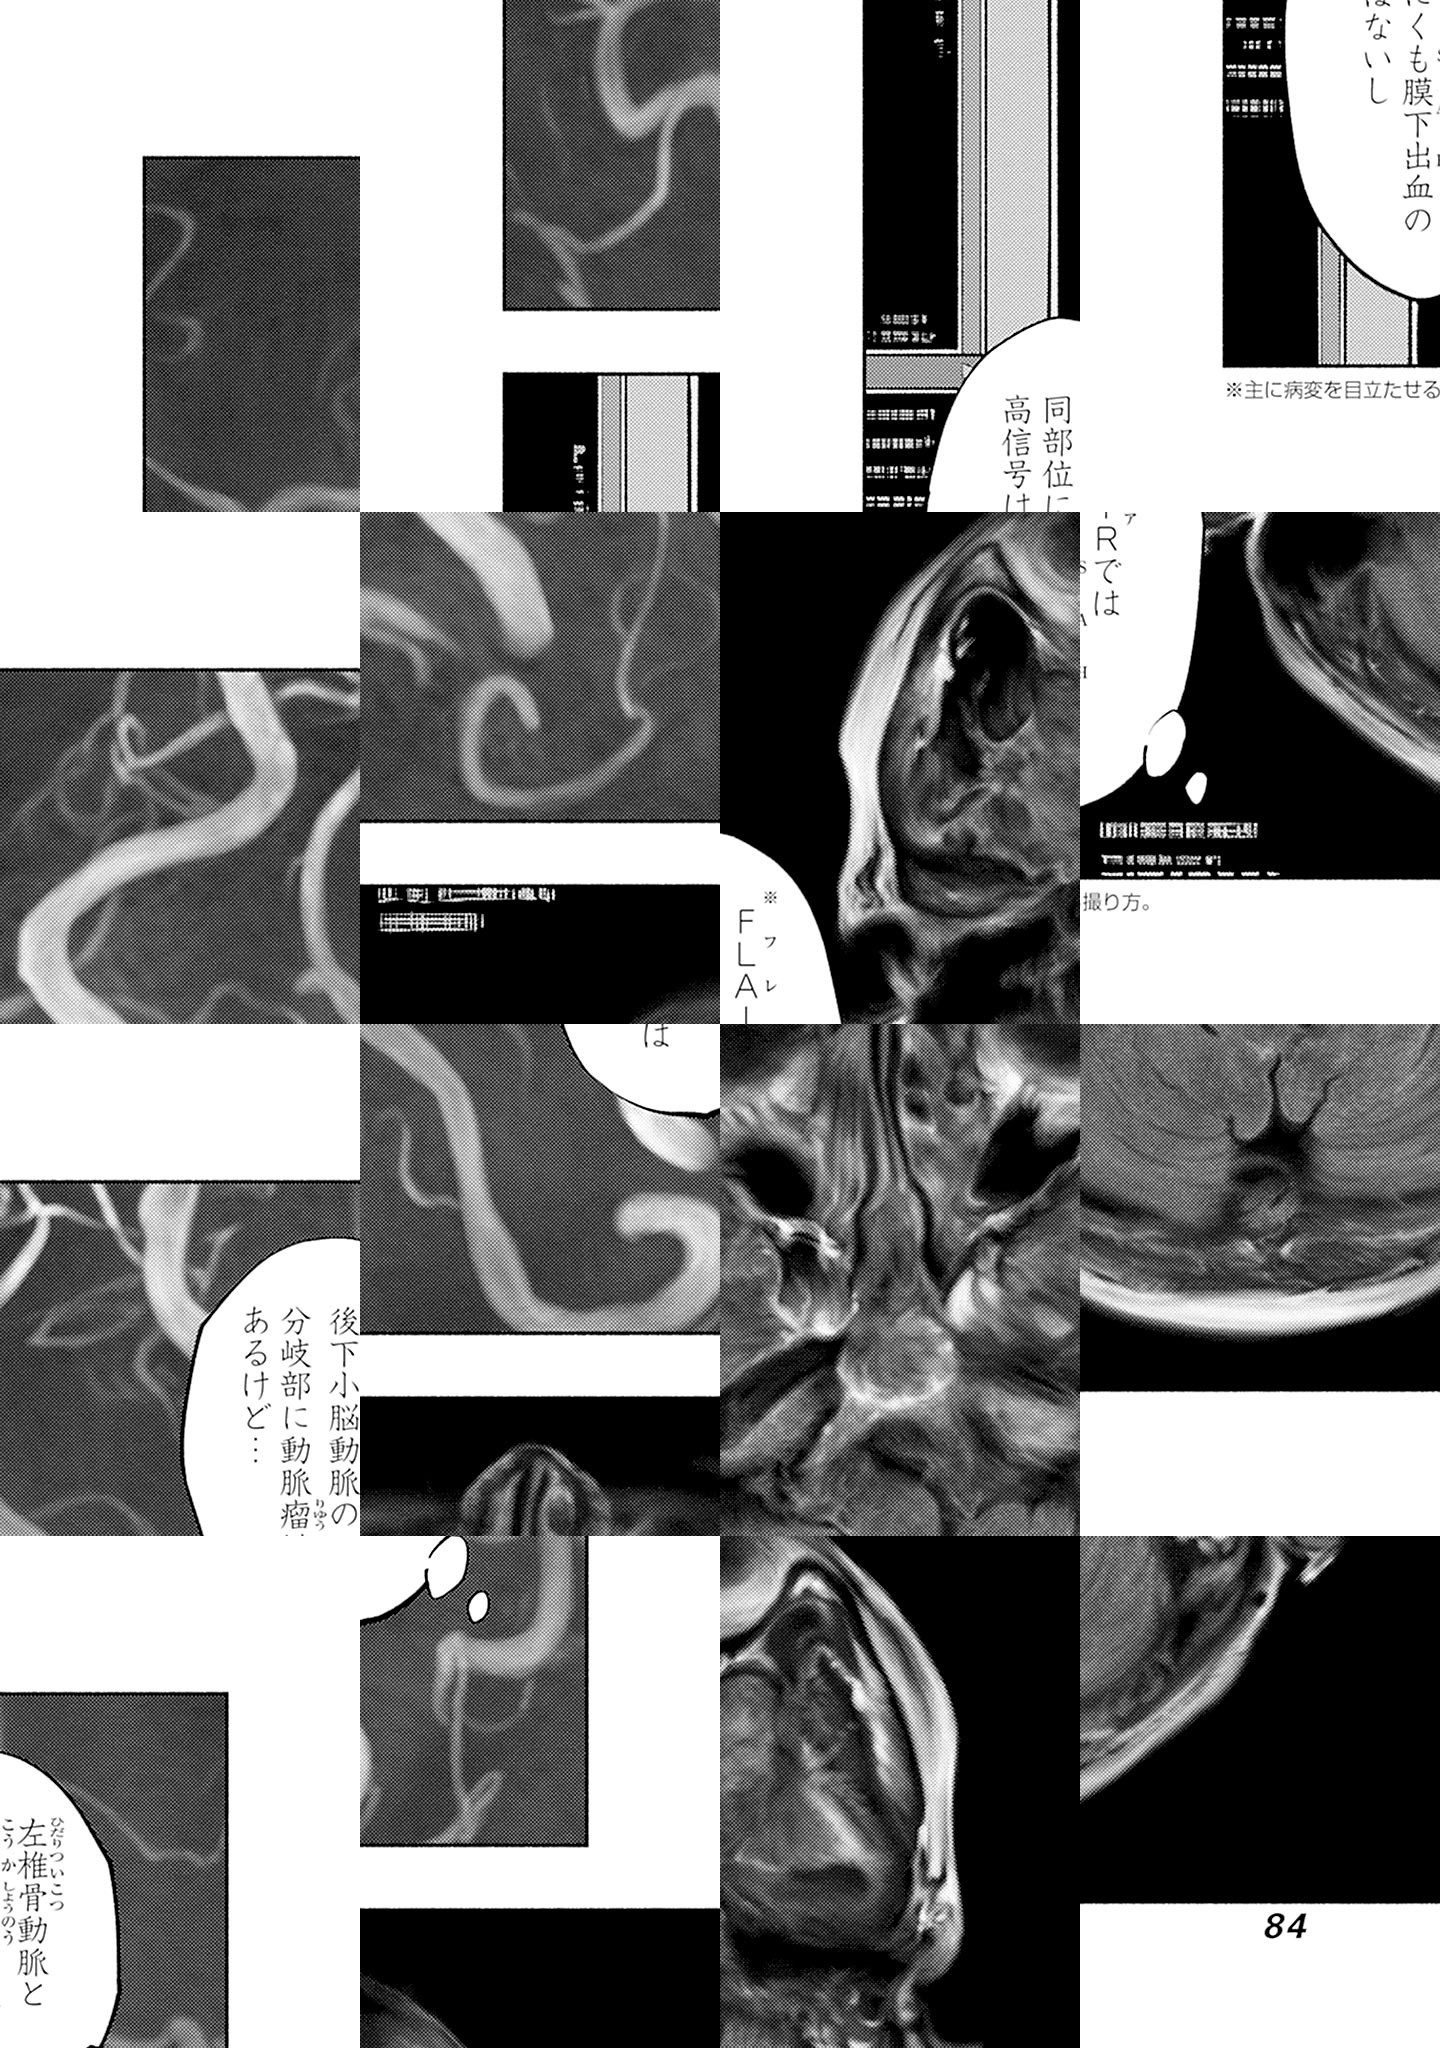

診療放射線技師・五十嵐唯織。CTやMRIを撮る腕は超一流だがコミュ障の彼は、憧れの幼馴染・甘春杏が放射線科医として勤める病院に採用される。そこで、彼女を技師として支えようとする唯織だが…!? 視えない病を診つけ出す、画像診断医療コミック開幕!!

第137話 当直戦線、異状なし!?④